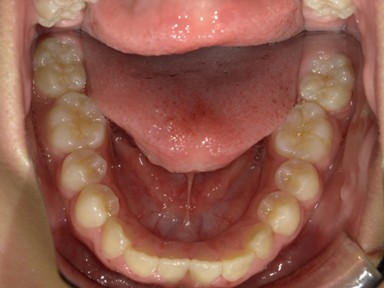

| 主訴 | 受け口を治したい。 |

| 治療内容 | ・使用装置:- マイオブレース(J1, J2) ・ワイヤー矯正および拡大装置等:未使用 ・抜歯:なし |

| 治療費 | 110,000円(税込み) |

| 治療期間 | 2017年9月~2018年8月(現在も定期的に保険にて観察中) |

| 治療回数 | 10回 |

| 想定されたリスク | マイオブレースの装着状況によっては結果が得られず、その他の矯正器具を使用する可能性がありました。 |

乳歯の反対咬合は様子を見ましょうと言われることが多いですが、上顎の前方発育を阻害する大きな要因となりますので、早期の介入をおすすめしています。反対咬合は1年で改善し、現在は定期健診で様子を見ています。装置を付けることなく、良好に生え変わりが進んでいます。